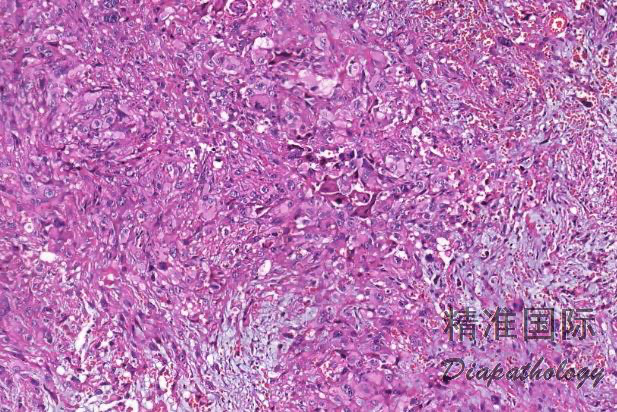

组织学上上皮样肉瘤由多边形上皮样细胞和多少不等的梭形细胞组成,根据形态不同可分为经典型、血管瘤样变型、纤维瘤样变型和近端型四种亚型。

经典型:

瘤细胞呈结节状或花环样排列,结节周围围绕胶原纤维,结节中央常伴有坏死;

肿瘤由上皮样细胞和梭形细胞共同组成,上皮样细胞呈多边形、卵圆形或胖梭形,胞质丰富,深嗜伊红色,和梭形细胞间有移行;细胞核轻度异型,呈空泡状,可见小核仁,核分裂像通常少于 5/10HPF;

间质可见嗜伊红色的胶原纤维;

近端型:

呈多结节性,以上皮样细胞为主,梭形细胞少;

上皮样细胞大而圆,有明显的异型性,染色质呈空泡状,可见明显的核仁,常见坏死;

部分区域可见横纹肌样瘤细胞,当横纹肌样瘤细胞较多时,可称为具有横纹肌样上皮样肉瘤。